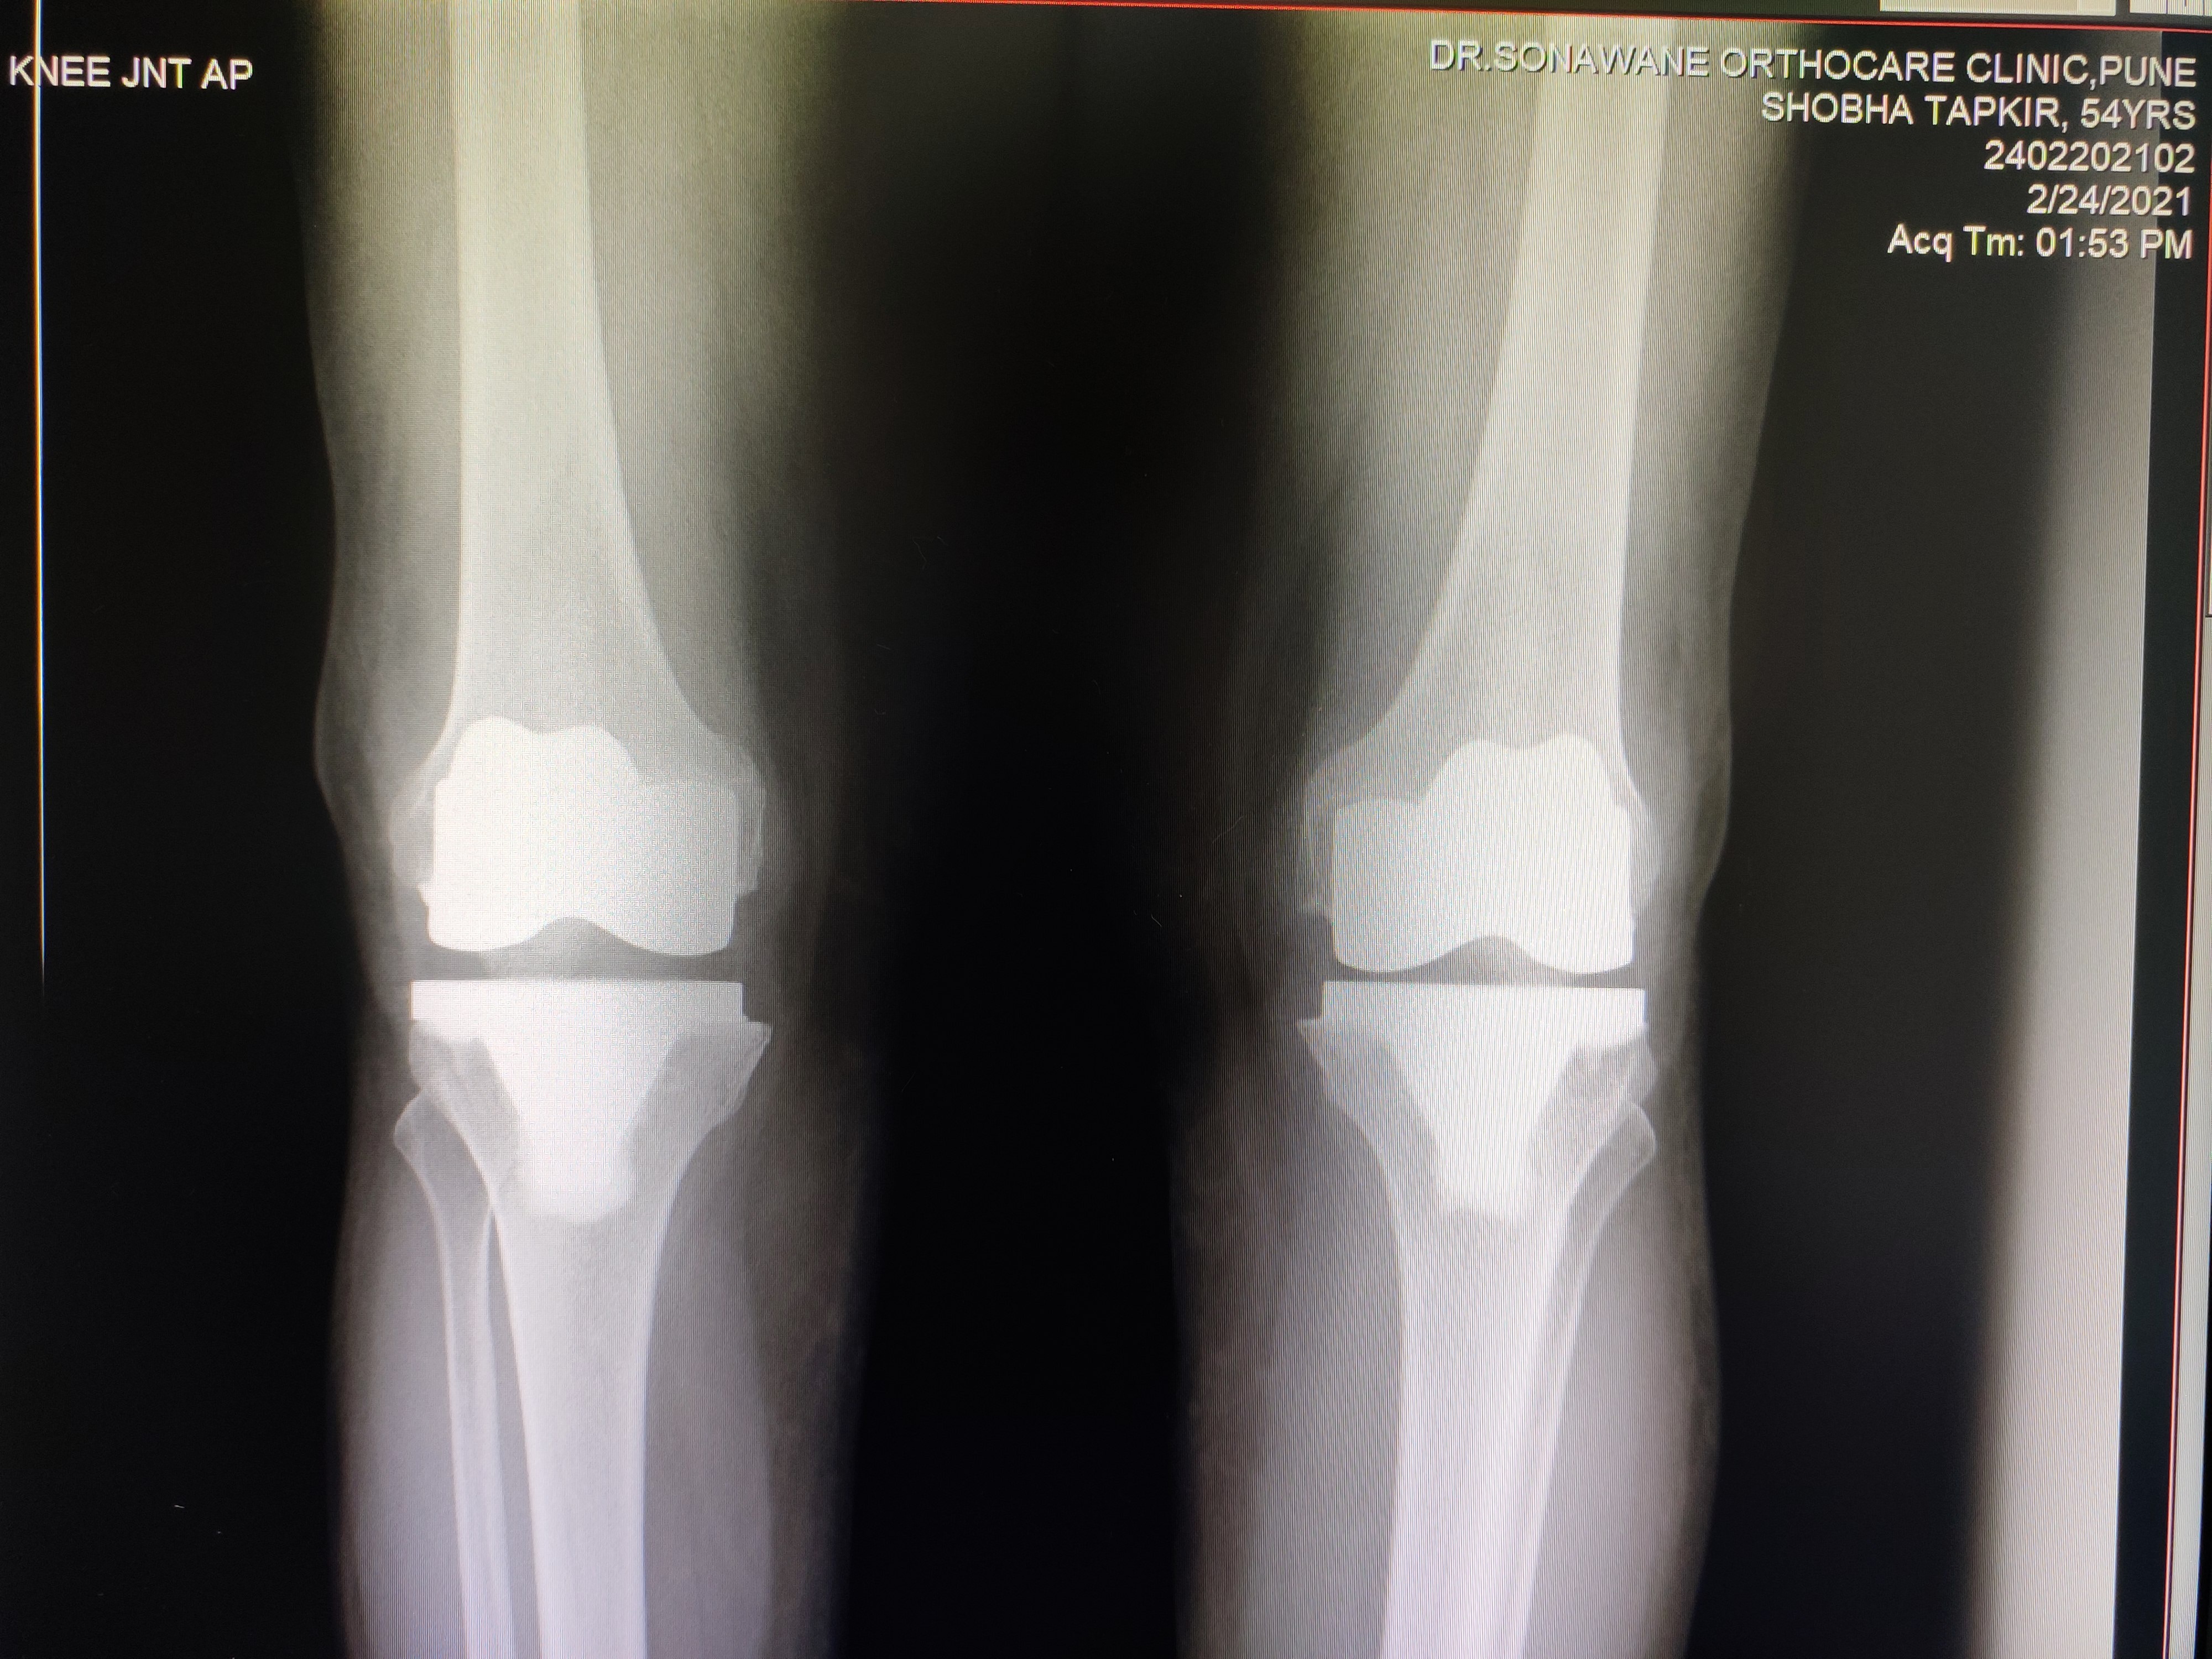

Dr. Sonawane Orthocare clinic is a centrally located Orthopedic Clinic In Pune city near Swargate at Hirabaug Business Centre, Hirabaug chowk, Tilak Road, Shukrawar peth and has easy accessibility from all parts of the city with multiple modes of travelling and enough parking spaces for patients’ own vehicles. Clinic is very modern and stylish and has air conditioned waiting area with comfortable sitting arrangement along with other amenities like TV, Wi-Fi, newspapers. There is hassle-free appointment and consultation system which is totally computerized. Patients get system generated appointment messages, reminders for follow-up dates and prescriptions through messages and emails. So its easy to keep track, keep and carry records and access it anywhere in the world. Clinic offers in-house digital X-ray, pathology tests and physiotherapy facilities at very reasonable rates. This makes the clinic a one stop destination for the patients they don’t need to go anywhere else for these facilities, saving lots of time and effort to get the treatment. We at Dr. Sonawane Orthocare clinic are committed for the best orthopedics care and proud to be one of the best orthopedics clinics in Pune.